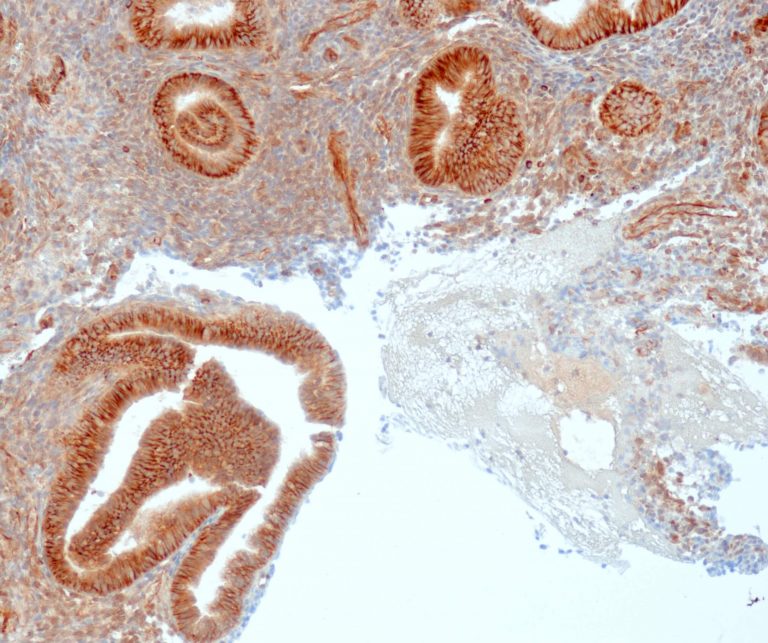

Gastrointestinal (GI) Pathology